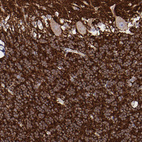

Immunohistochemistry analysis in human cerebral cortex and testis tissues using HPA001830 antibody. Corresponding SNAP25 RNA-seq data are presented for the same tissues.